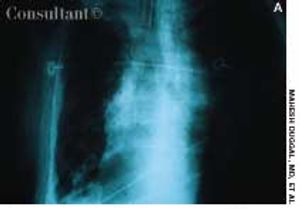

A 65-year-old man was hospitalized with dyspnea and fever of a few days' duration. He complained of excessive malaise, fatigue, and weight loss but denied any hemoptysis. The patient had a history of alcohol abuse.